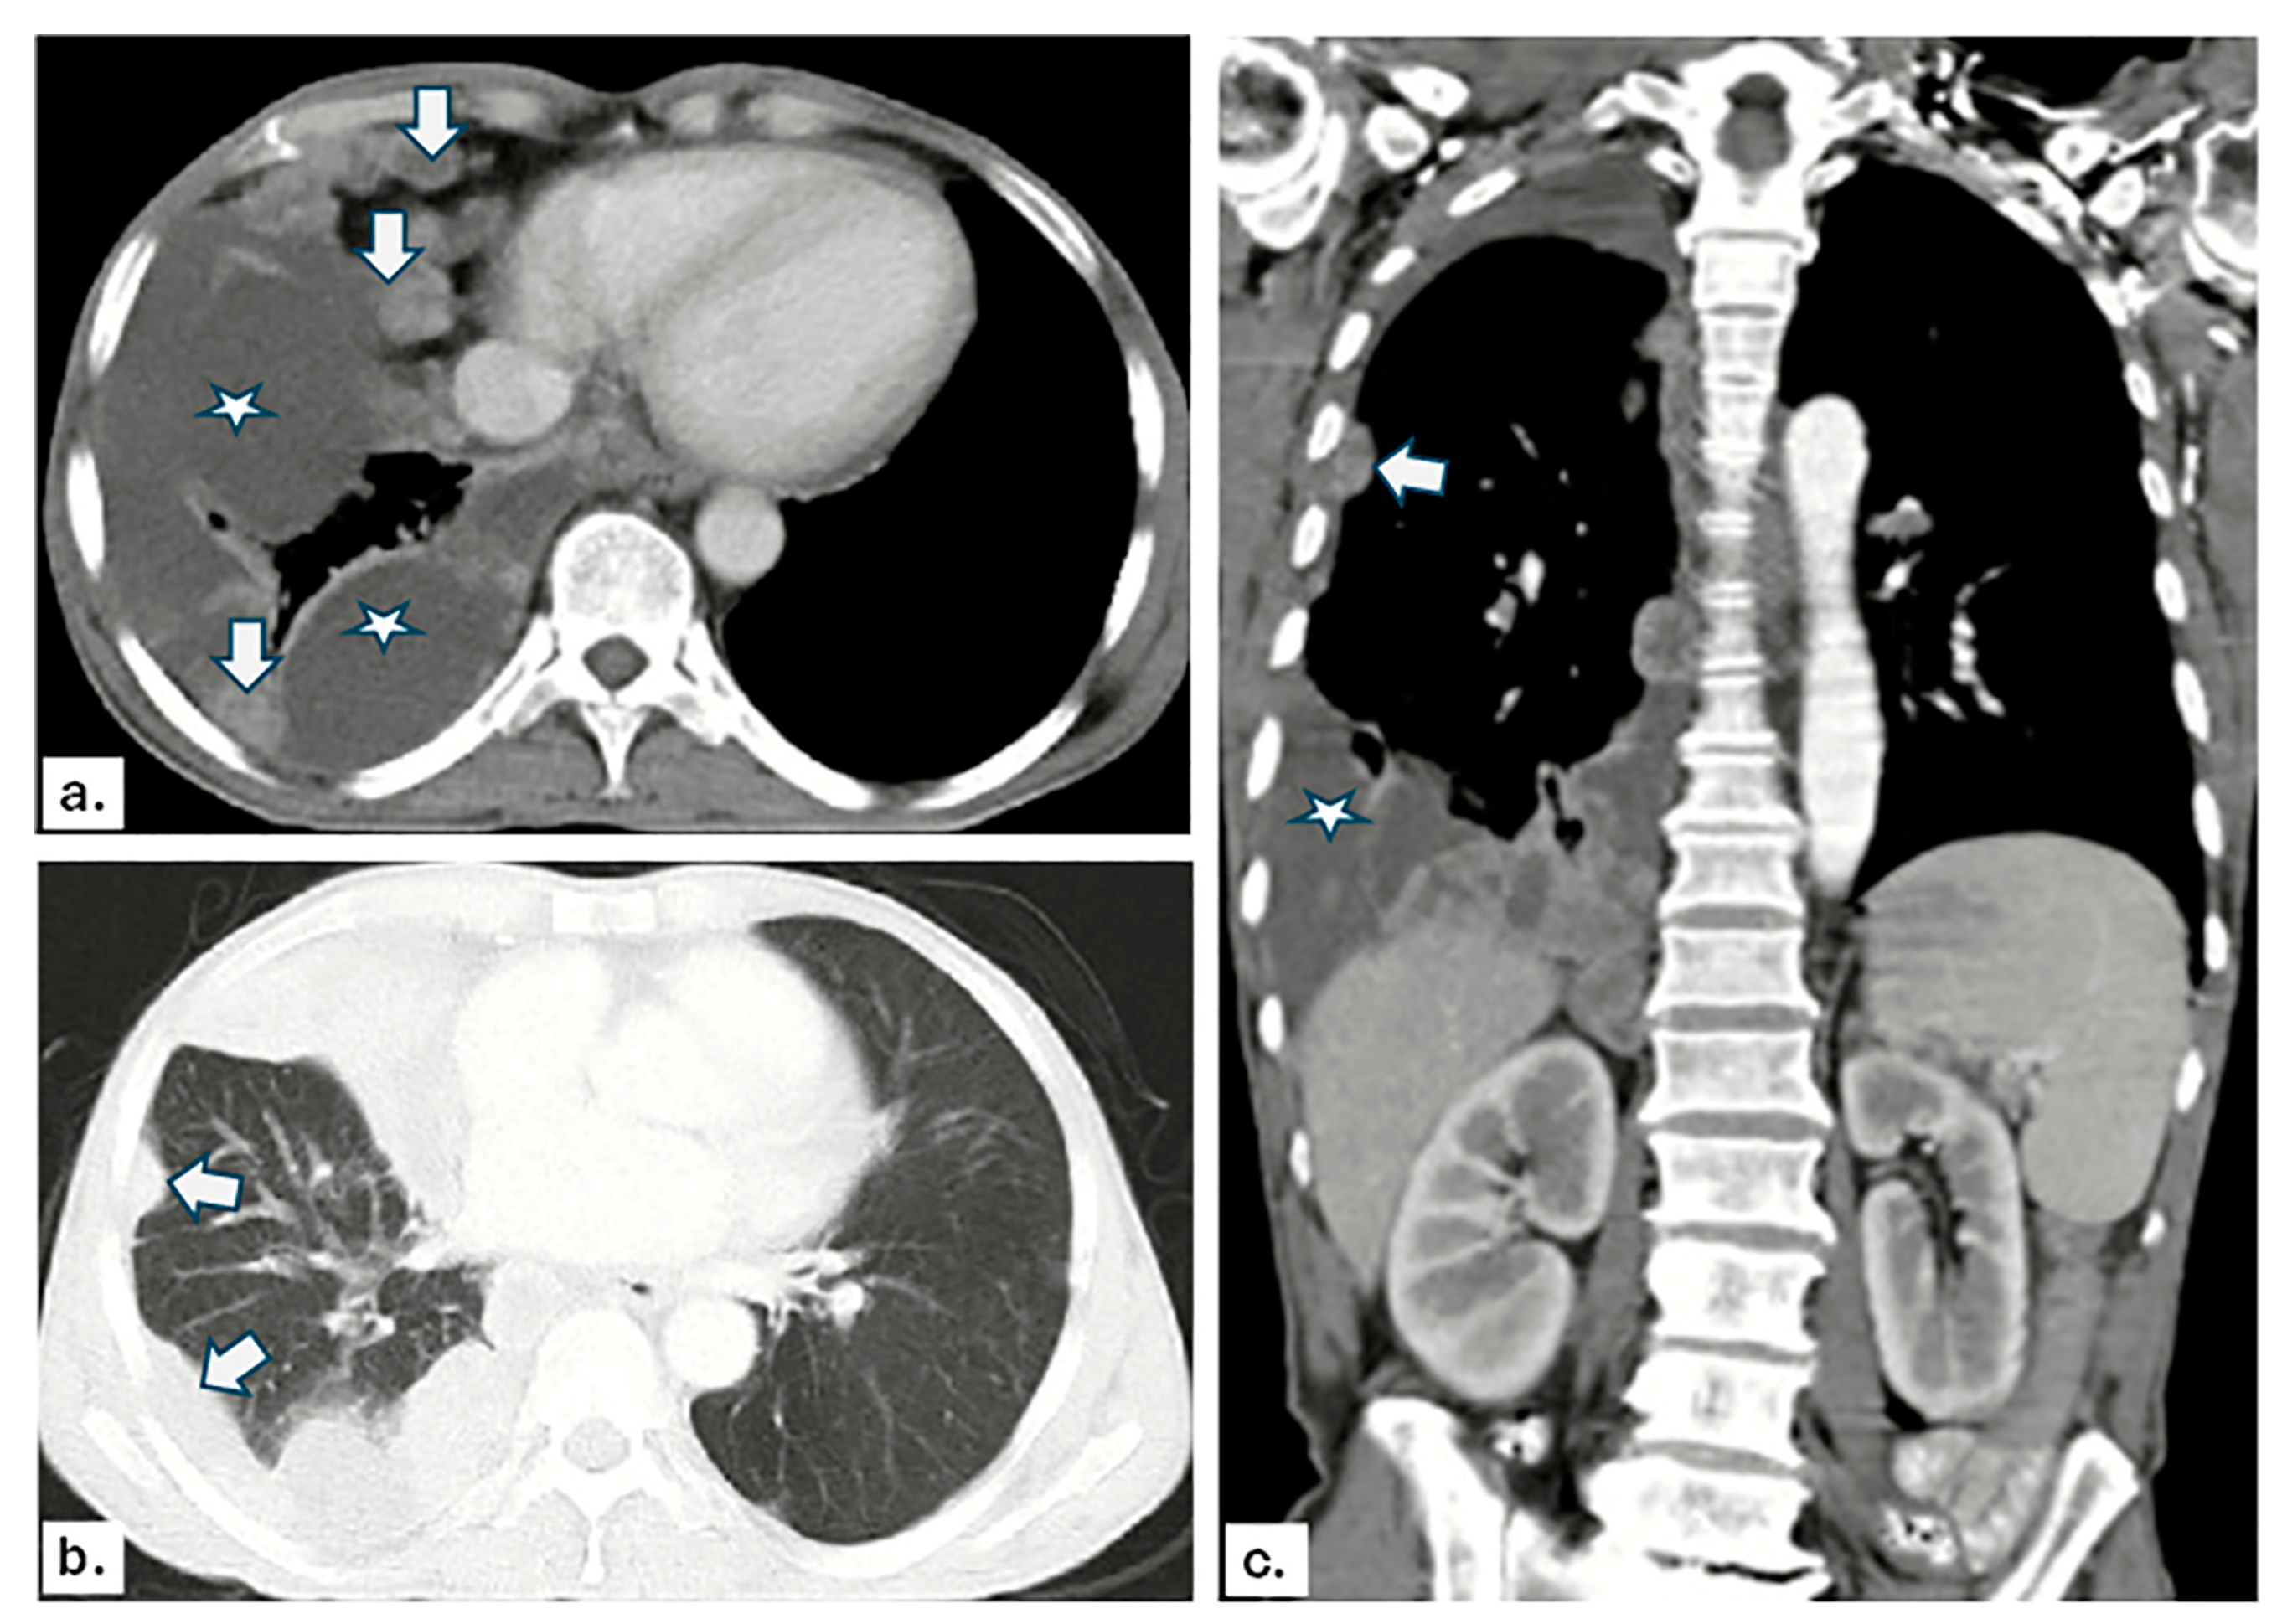

2.5. CT Image Analysis

3.2. US and CT Findings in MPE

3.3. Imaging Findings in Benign Pleural Effusion